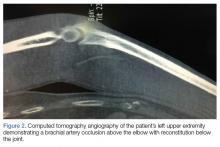

Computed tomography angiography of the left upper extremity showed a brachial artery occlusion above the elbow, with reconstitution below the joint (Figure 2).

Figure 2.